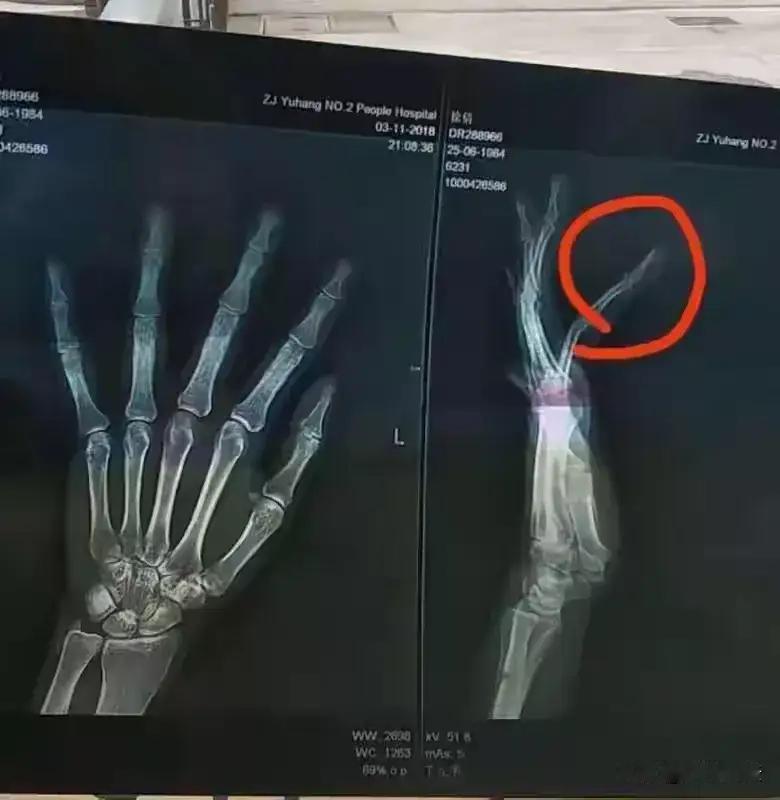

“这就是嚣张的下场!”浙江,一女子带6岁儿子散步,一条哈巴狗追咬孩子,女子做了一个抬脚驱赶姿势,岂料,狗主人却说女子踢狗,还说狗是他儿子,随后竟疯狂殴打女子,骑在她身上对其拳打脚踢,将女子手指打残疾,事后男子被刑拘,而法院判决大快人心! 这起事件,表面看似简单的“狗咬人引发的纷争”,背后却折射出社会中关于公共安全、文明养犬以及法治意识的深层问题。我们常说“文明养犬,共同守法”,但当“养犬人”的行为冲突与自己对“权利”的错认交织,就极易酿成悲剧。从女子被狗吓到本能反应驱赶,到狗主大打出手疯狂施暴,暴力背后的冷漠与狂妄令人震惊。 更令人愤慨的是,狗主的不理性不仅伤害了无辜的母子,更公然挑战法律权威、践踏受害者尊严。把“狗是他儿子”当作抵抗暴力的借口,无异于把理性和法纪踩在脚下。这样的行径让人想起许多因“私人情绪”失控而导致极端暴力的悲剧,它既是个人心理问题的爆发,更是社会治理漏洞显现的警钟。 同时,也引发群众对“公共空间安全”的深切关注。遇到流浪狗或他人养的宠物突然靠近孩子或老人,家长们该如何保护自己孩子安全而不失理智?社会应该如何加强责任宠物主的文明养犬教育和制度监管?这其中,不仅仅是简单的个案,更是关系到每个市民利益的大问题。 法院的果断判决不仅让受害的女子得到了应有的正义回应,也为我们树立了坚决打击暴力行为、保护弱势群体的法律标杆。法律是社会公平公正的底线,是每个人都不可逾越的红线。只有人人尊法守法,社会才能真正远离冷漠与暴力。 然而,最让人痛心的是,这样的事件依旧时有发生。或许我们每个人都应反思:当公共利益与个人情绪发生冲突时,我们到底应该如何权衡处理?是选择暴力发泄,还是以理性沟通解决?这个社会需要更多的温度,更强的法治精神,更成熟的公民意识。 最后,愿这起事件成为我们的警钟。文明不是一句口号,而是日常行为的体现;法治不是虚设的威慑,而是我们共同的保障。在公共场所,每一份理智与克制,都是对生命和尊严的尊重,是铸就幸福社会不可或缺的基石。希望更多人看到真相背后的深意,怒斥暴力的同时,也积极思考如何做一个有责任、有担当的公民。你怎么看?欢迎留言吐槽,一起为更文明、更安全的社会出声! [相片人物均为化名] 恶狗撕咬女童 大狗撕咬小女孩 狗嫌弃的熊孩子 女童遭狗群撕咬